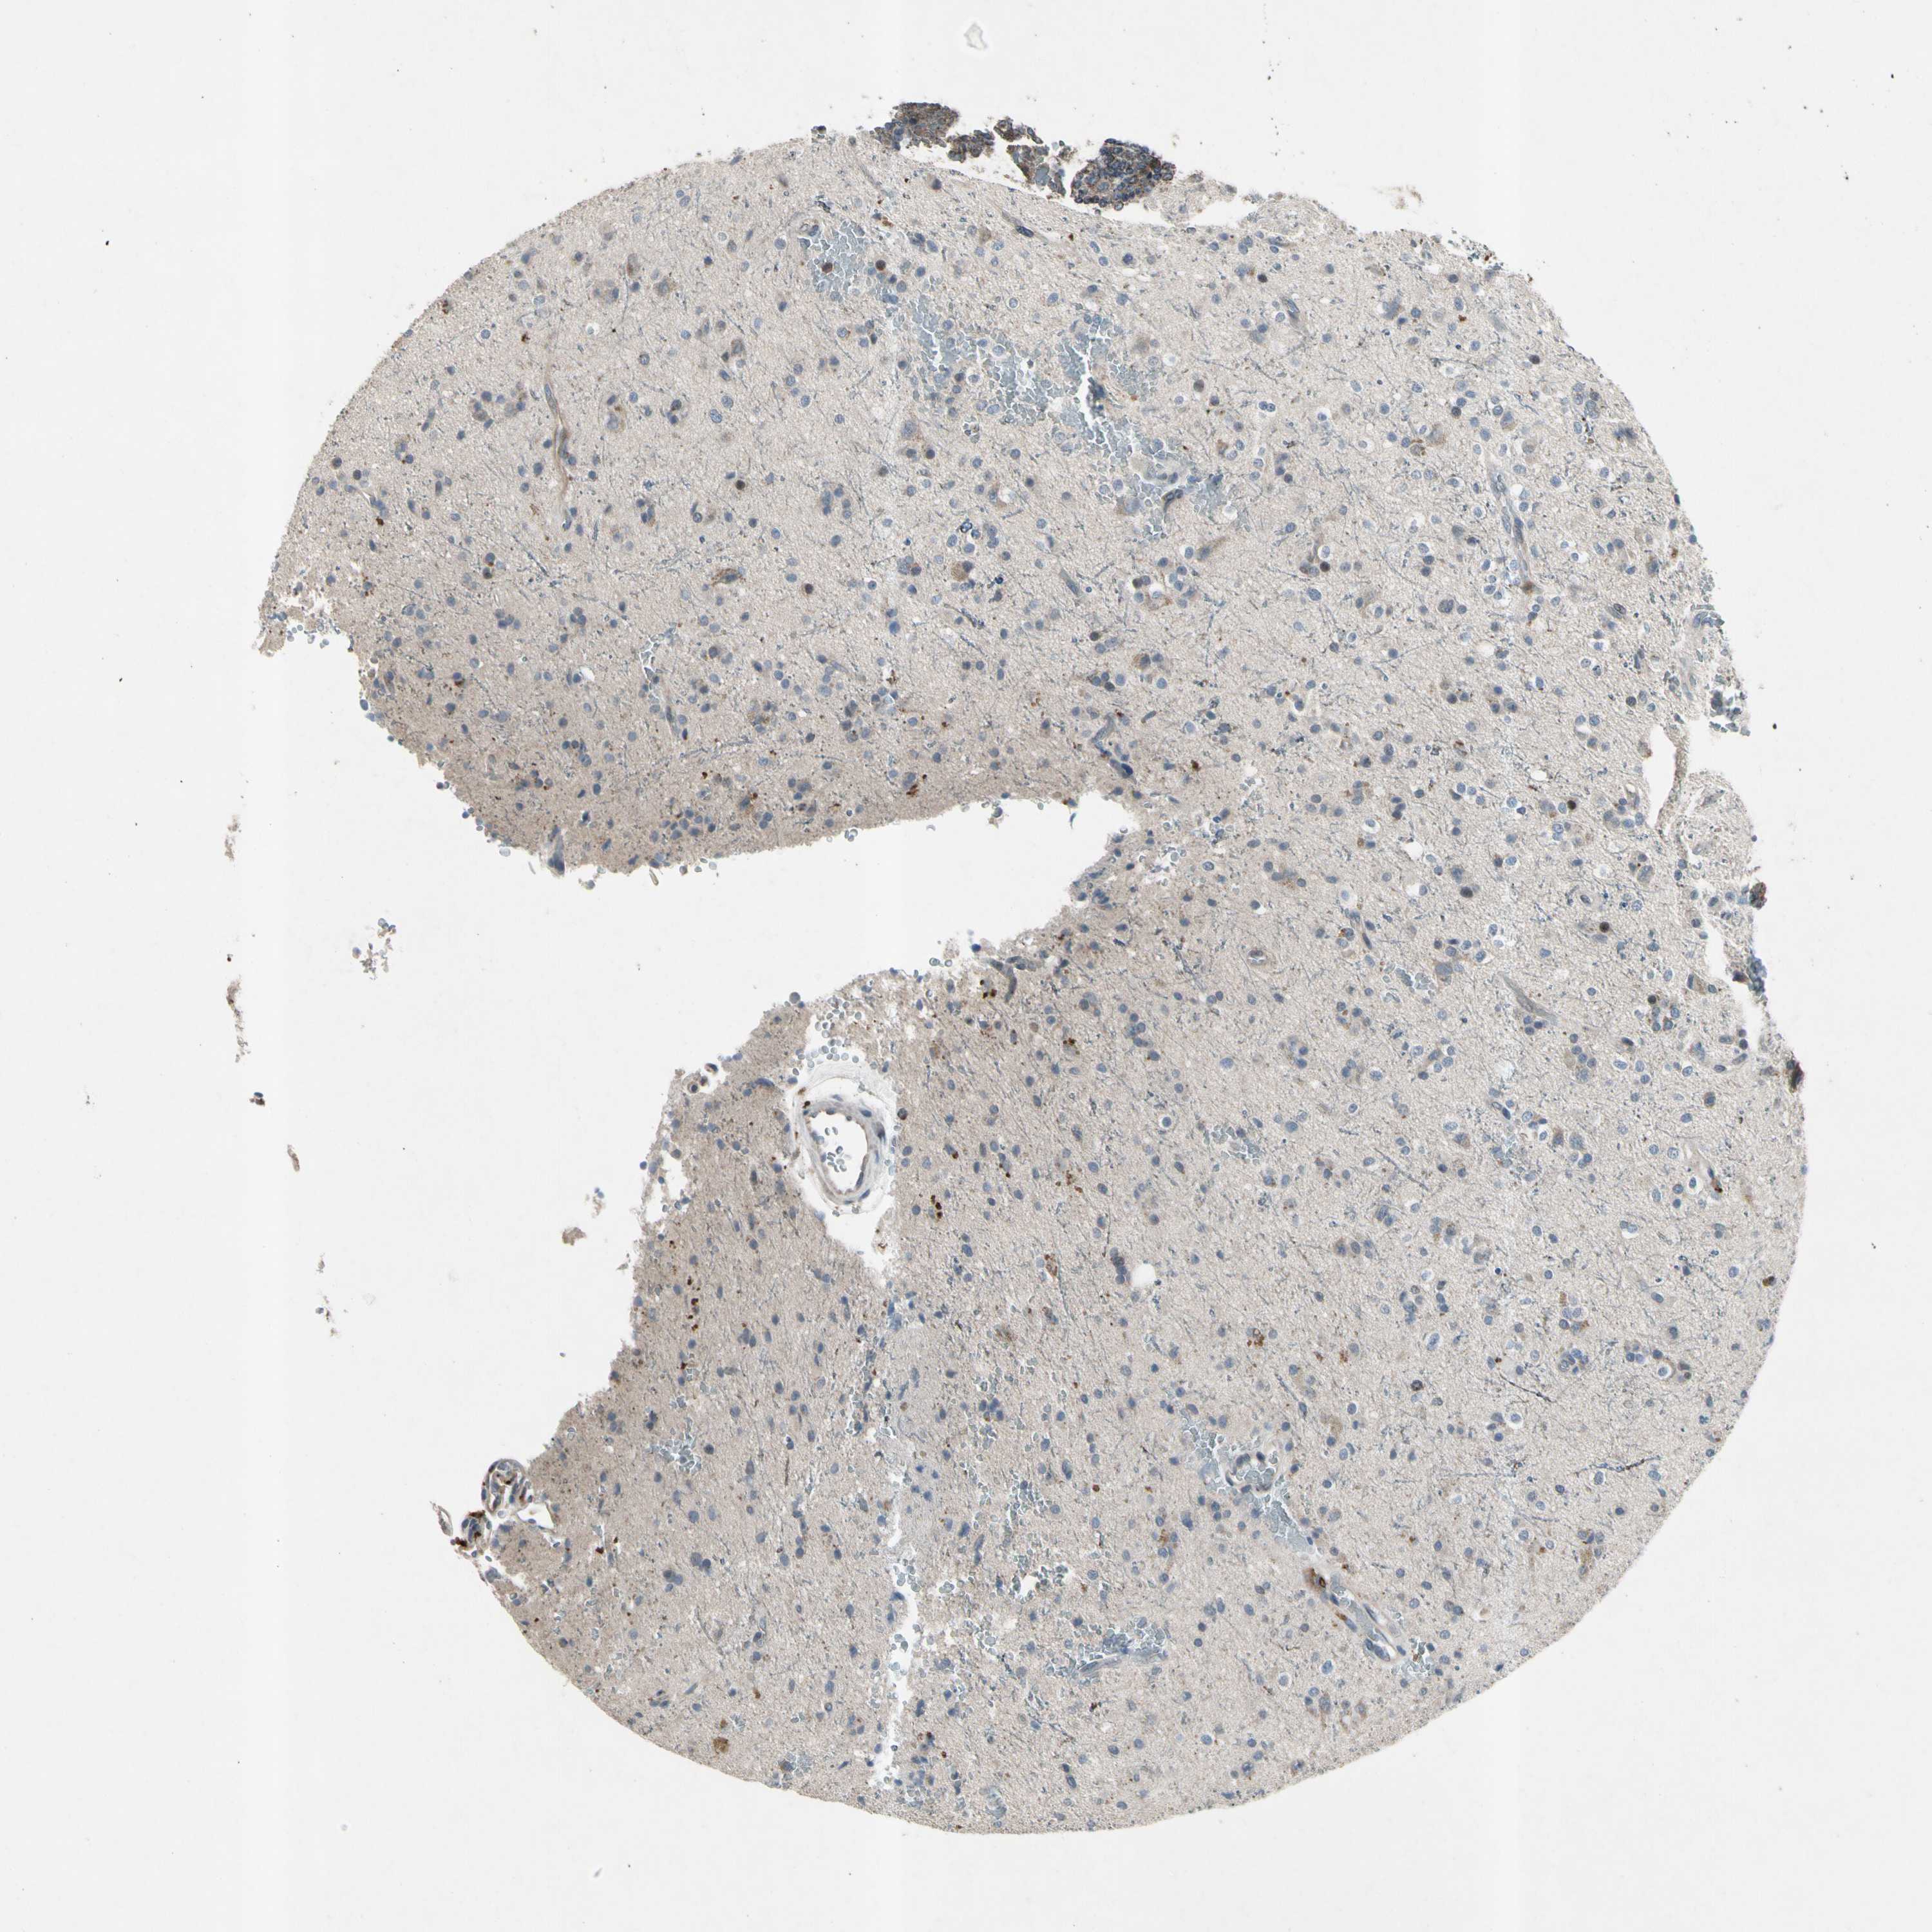

GLIOMA - Protein expressioni

A mouse-over function shows sample information and annotation data. Click on an image to view it in a full screen mode. Samples can be filtered based on level of antibody staining by selecting one or several of the following categories: high, medium, low and not detected. The assay and annotation is described here.

Note that samples used for immunohistochemistry by the Human Protein Atlas do not correspond to samples in the TCGA dataset.

Antibody stainingi

Antibody staining in the annotated cell types in the current human tissue is reported as not detected, low, medium, or high, based on conventional immunohistochemistry profiling in selected tissues. This score is based on the combination of the staining intensity and fraction of stained cells.

Each image is clickable and will lead to virtual microscopy that enables deeper exploration of all samples and also displays staining intensity scores, fraction scores and subcellular localization as well as patient and tissue information for each sample.

Antibody HPA008588

Staining

High

Medium

Low

Not detected

Intensity

Strong

Moderate

Weak

Negative

Quantity

>75%

75%-25%

<25%

None

Location

Nuclear

Cytoplasmic/membranous

Cytoplasmic/membranous,nuclear

Glioma, malignant, High grade

Glioma, malignant, Low grade